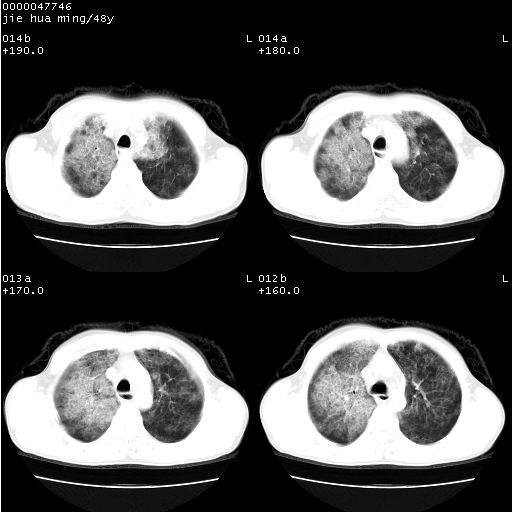

以下是引用hhcckk在2008-5-1 8:06:00的发言:[br]支持肺泡蛋白沉积症[br]依据:[br]1、病灶边缘清楚----地图征[br]2、病灶内部小叶间隔或小叶内间隔增厚所形成的网格状影----碎石路样表现[br]3、抗炎治疗无效(炎症抗炎治疗有效)[br]4、纵隔内未见肿大淋巴结(肺泡细胞癌时常有)[br][br]附肺泡蛋白沉积症资料[br][br]肺泡蛋白沉积症(pulmonary alveolar proteinosis)是一种原因不明的以肺泡腔内大量含脂糖蛋白样物质沉积为特征的疾病。[br]病理改变:(1)肺泡和细支气管腔内充满大量含脂糖蛋白样的粘稠物质,该物质为颗粒状或絮状的糖原pas染色阳性的磷脂蛋白。(2)肺泡壁及其间隔无异常改变。胸膜和淋巴结不受累及。(3)晚期可出现弥漫性肺间质纤维化。[br]临床表现:(1)好发年龄30~50岁,男性多于女性,偶见于儿童;(2)主要症状为呼吸困难、咳嗽、低热、消瘦、低氧血症和杵状指等。1/3的患者无症状。(3)实验室检查:痰液或肺泡灌洗液中可找到pas染色阳性颗粒物质。[br]hrct表现:肺泡蛋白沉积症具有特征性改变,即“碎石路样”表现(crazy-paving appearance,cpa)。主要包括(1)斑片状磨玻璃影:指肺野密度朦胧增加,内可见肺血管纹理影,系肺泡腔内充满低密度的磷脂蛋白物质所致。(2)其内部小叶间隔或小叶内间隔增厚所形成的网格状影,为小叶间隔水肿、肺泡壁内淋巴细胞和巨噬细胞浸润以及小叶内淋巴管扩张的缘故。(3)病灶边缘清楚,呈地图样分布于肺野外围或肺门及中央区。[br]

以下是引用zsl6918在2008-5-1 7:35:00的发言:[br]双肺磨玻璃样病变,可见铺碎路石征,病变区与正常区交错。边界清晰。符合肺泡蛋白质沉着征,高分辨扫描会更清楚漂亮。建议临床肺泡灌洗。

以下是引用yangyudong333在2008-5-1 5:36:00的发言:[br][br] 两肺广泛毛玻璃样的片状影,密度不均,边缘欠清,呈碎石路样改变,[br]考虑,1双肺间质性肺炎,2肺泡蛋白沉积症[br]